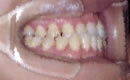

交叉咬合

初診時、向かって左側の噛み合わせが逆になっている交叉咬合を示し、顔貌においても

下顎の偏位を示していました。